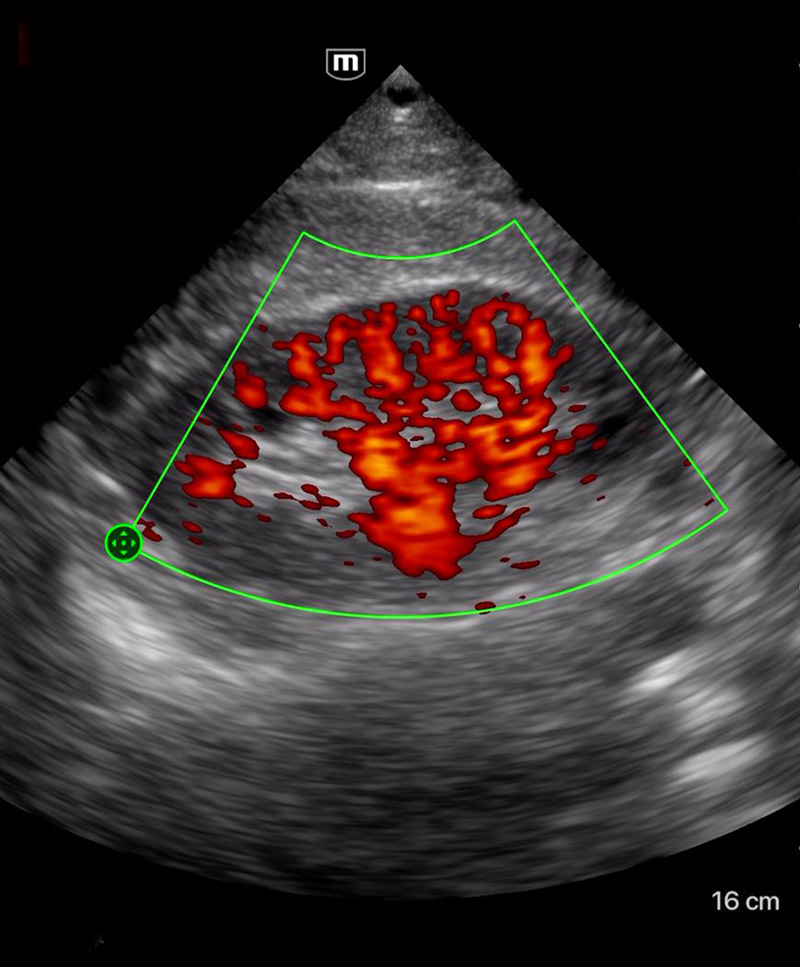

Clinical Images

Dilated Cardiomyopathy

Clinical Images

Dilated Cardiomyopathy